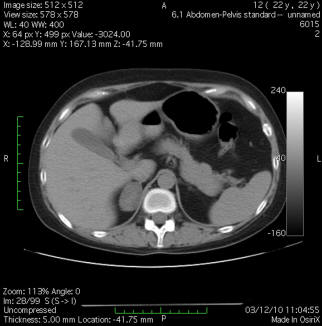

Cushing's Syndrome Dueto Autonomous hyperplasia: Long-term ...

Autonomous macronodular adrenal hyperplasia 615 Figure 1 Abdominal CT imaging. Bilateral A but asymmetrical diffuse enlargement of adrenal Gb glands. Notea small nod- ... View This Document